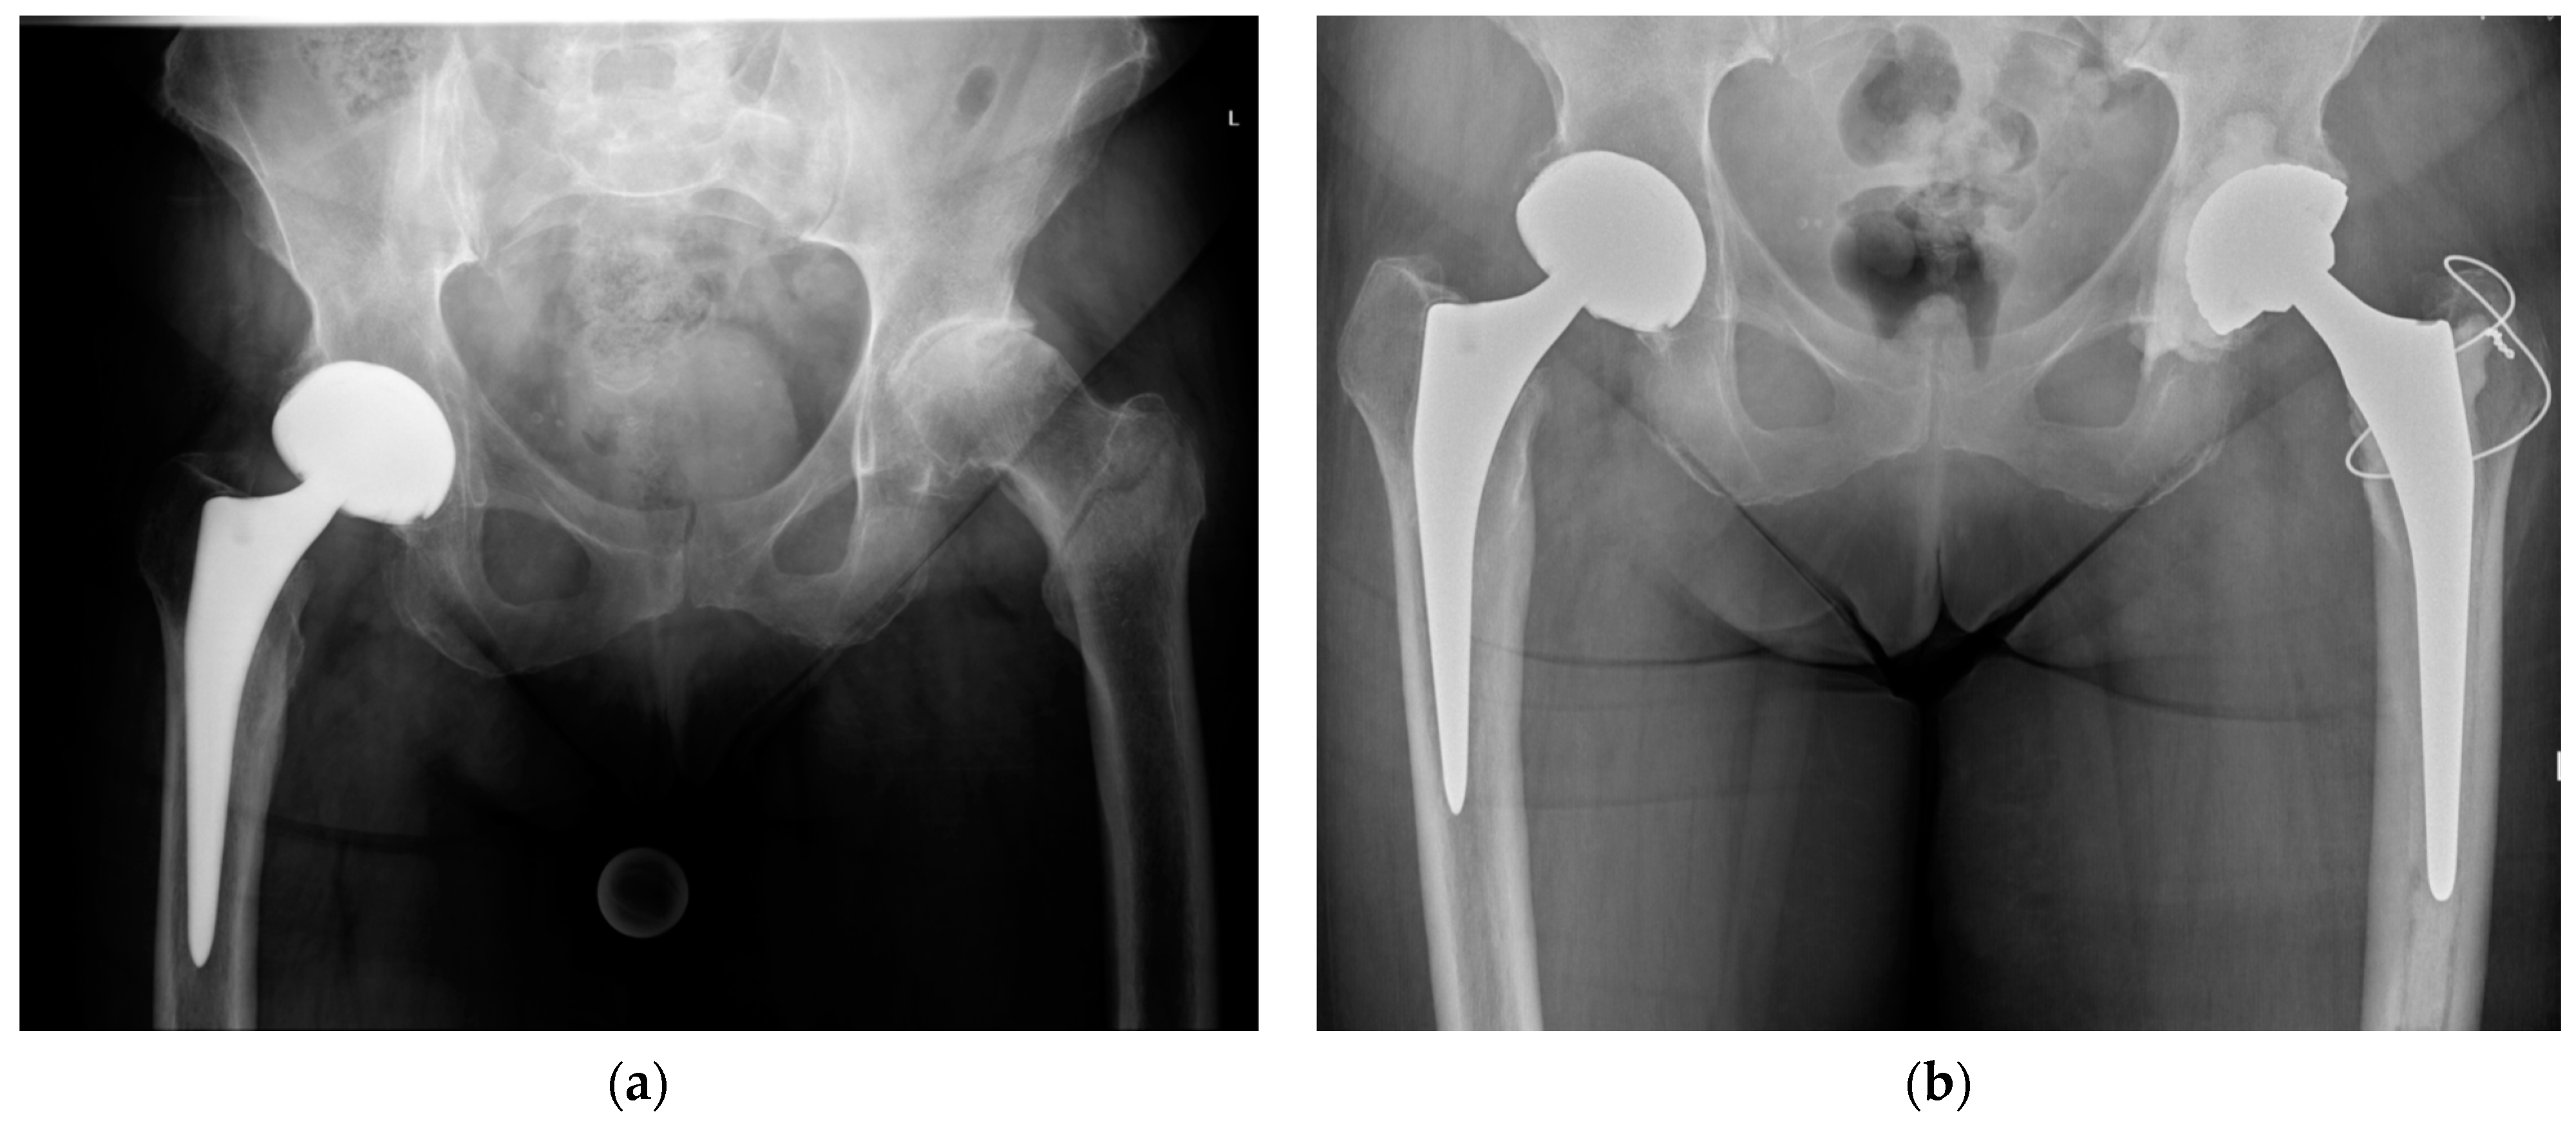

Various designs of primary and revision femoral stems have been used successfully for the treatment of IFFs. Grote et al. [21] compared cemented primary stems with revision stems to treat unstable IFFs without finding a significant difference in complication or reoperation rates. Nevertheless, IFFs are often associated with bone loss in the proximal femur that may present a challenge for prosthesis anchoring. Most authors thus recommend adapting the length of the stem to the fracture pattern, particularly to the distal extension of the fracture line and the bone stock (Figure 2). Diaphyseal fixation or calcar replacement stems are suitable options in situations where the metaphysis is significantly compromised. Modular revision femoral stems have the advantage of allowing to first impact the stem into the diaphysis until it is stable so that the length, version, and offset of the overall femoral component can be adjusted through the proximal body in a second step.

Figure 2.

(a) Preoperative anteroposterior pelvic radiograph of an intertrochanteric femur fracture with concomitant osteoarthritis of the left hip; (b) postoperative anteroposterior pelvic radiograph after total hip arthroplasty with a cemented femoral stem, fixation of the greater trochanter by a figure-of-eight wire cerclage, and a cemented acetabular cup.